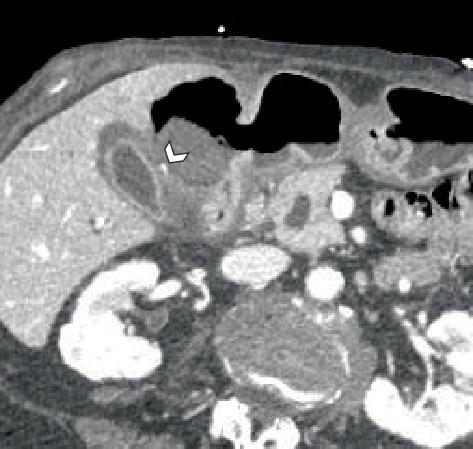

This case study presents an 87-year-old female patient with a history of chronic abdominal pain and NSAID use who was admitted with symptoms of hematemesis and melena, indicative of upper gastrointestinal bleeding. Upon examination, she was found to be hemodynamically stable but exhibited signs of moderate protein-calorie malnutrition. Imaging studies, including a multiphasic CT angiogram, revealed a contained rupture in the distal stomach, and a cystic artery pseudoaneurysm measuring 4.2 mm. Despite the presence of a perforated ulcer, there was no significant pneumoperitoneum or hemoperitoneum, leading to a diagnosis of contained perforation. The management plan included conservative treatment with IV antibiotics, proton pump inhibitors, and monitoring of hemodynamic status. On the third day of admission, the decision was made to embolize the cystic artery, as the risk of gallbladder ischemia was deemed low. This case underscores the critical need for prompt diagnosis and intervention in patients presenting with upper GI bleeding, particularly in the elderly, where the mortality rate can be significantly high. The findings emphasize the importance of imaging in localizing the source of bleeding and guiding appropriate management strategies.

本病例研究介绍了一位87岁的女性患者,有慢性腹痛病史且使用过非甾体抗炎药,因呕血和黑便症状入院,提示上消化道出血。检查发现,她血流动力学稳定,但有中度蛋白质 - 热量营养不良的体征。影像学检查,包括多期CT血管造影,显示胃远端有一处局限性破裂,以及一个4.2毫米的胆囊动脉假性动脉瘤。尽管存在穿孔性溃疡,但没有明显的气腹或血腹,诊断为局限性穿孔。治疗方案包括静脉使用抗生素、质子泵抑制剂进行保守治疗,并监测血流动力学状态。入院第三天,由于胆囊缺血风险被认为较低,决定对胆囊动脉进行栓塞。本病例强调了对上消化道出血患者,尤其是老年人,进行及时诊断和干预的迫切需求,因为老年人的死亡率可能显著较高。研究结果强调了影像学在确定出血源和指导适当治疗策略方面的重要性。